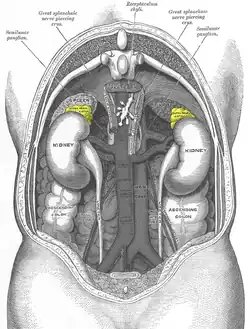

There are two adrenal glands, highlighted in yellow, on top of each of the kidneys